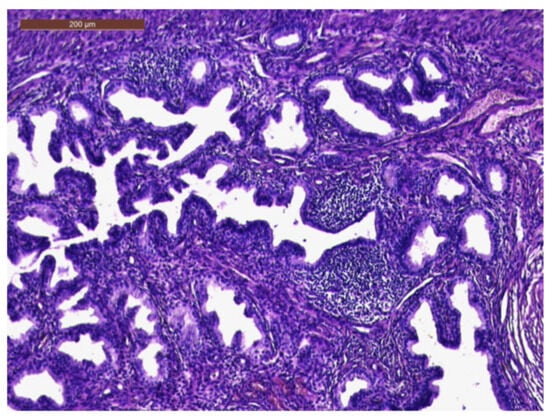

The histopathological exam revealed the tissue fragments to be sufficiently delimited by a thin layer of the endometrium composed of a biphasic stromal and glandular proliferation and represented by cellular stroma with edematous areas with thin blood vessels interspersed with thick bundles of smooth muscular fibers that included irregularly contoured secretory endometrial glands (Figure 4 and Figure 5), organized in hyperplastic lobular areas, and lined by the simple and pseudostratified epithelium with hyperchromatic nuclei (Figure 6), eosinophilic metaplasia, and a tendency for squamous differentiation.

Our microscopic findings are consistent with the following histopathological characteristics that define the atypical polypoid adenomyoma: a well-circumscribed biphasic tumor composed of endometrioid glands with a complex or lobular histoarchitecture, squamous morular metaplasia, and sometimes cytologic atypia, interspersed with a fibromyomatous stroma, which may present myxoid change.

Figure 5. Thick bundles of smooth muscle fibers interspersed with endometrial areas containing irregularly oriented glands and dense cellular stroma (HE × 10).